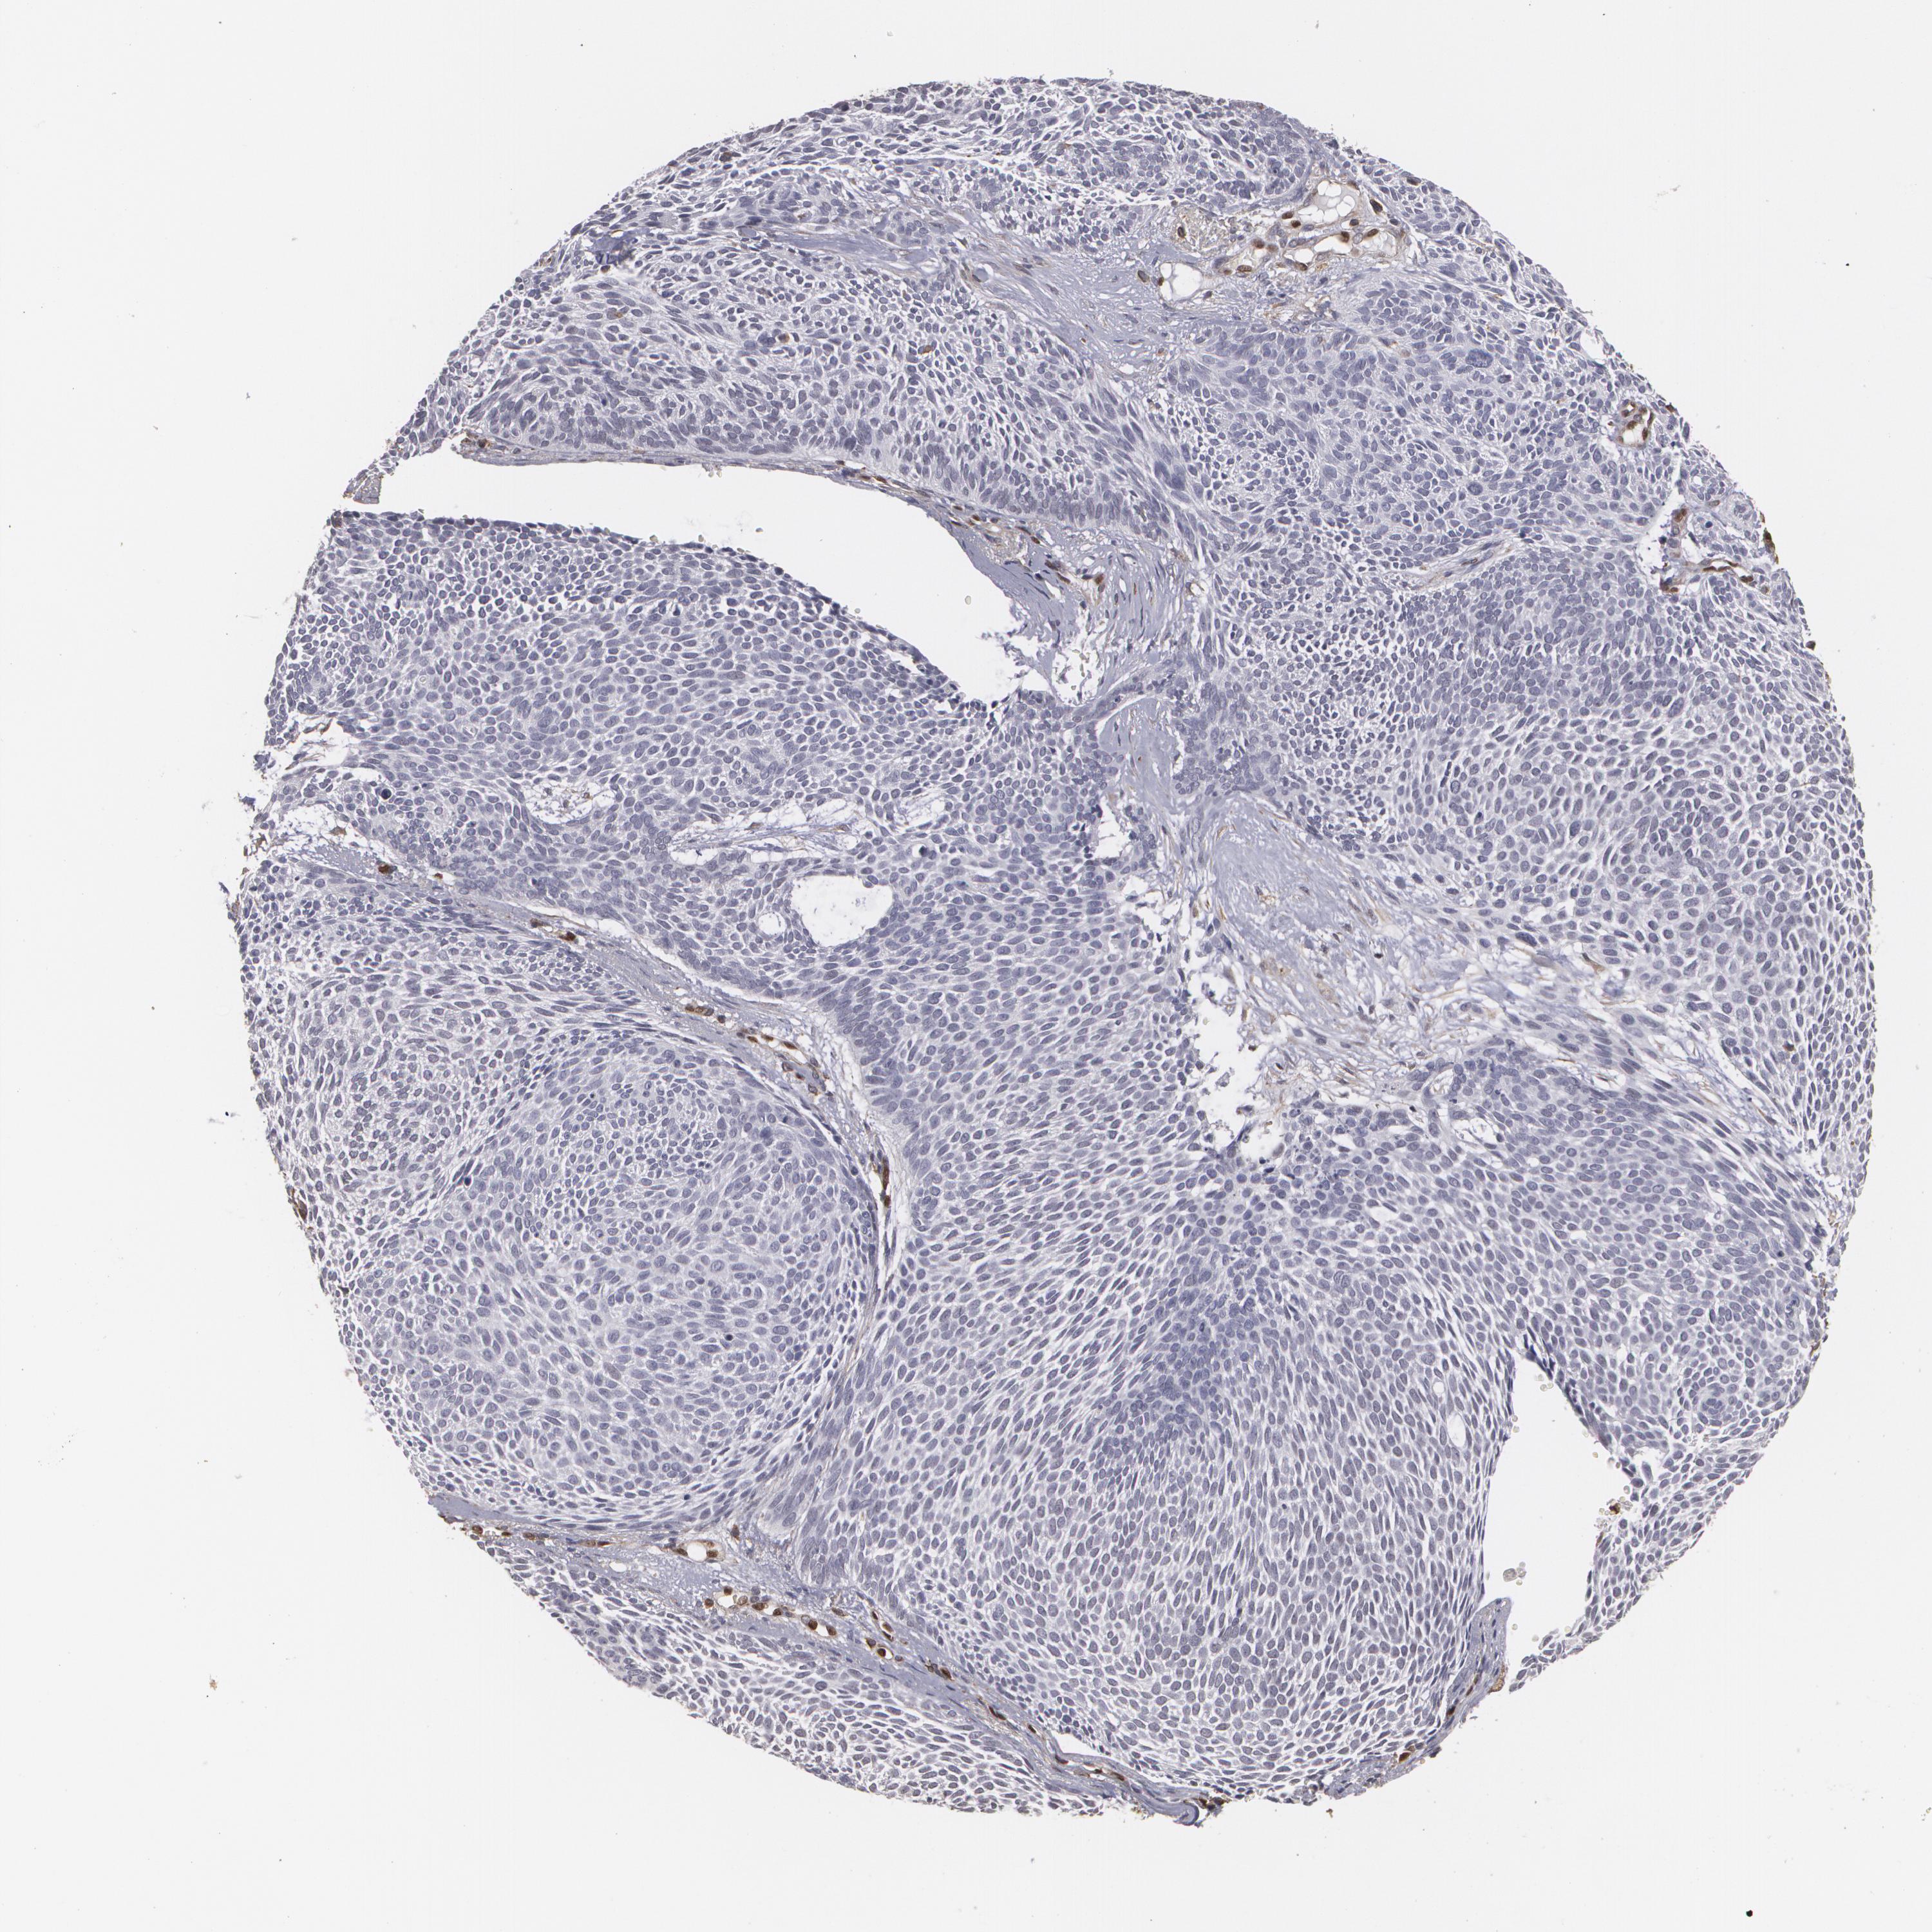

SKIN CANCER - Protein expressioni

A mouse-over function shows sample information and annotation data. Click on an image to view it in a full screen mode. Samples can be filtered based on level of antibody staining by selecting one or several of the following categories: high, medium, low and not detected. The assay and annotation is described here.

Antibody staining in the annotated cell types in the current human tissue is reported as not detected, low, medium, or high, based on conventional immunohistochemistry profiling in selected tissues. This score is based on the combination of the staining intensity and fraction of stained cells.

Each image is clickable and will lead to virtual microscopy that enables deeper exploration of all samples and also displays staining intensity scores, fraction scores and subcellular localization as well as patient and tissue information for each sample.

Antibody HPA001600

Staining

High

Medium

Low

Not detected

Intensity

Strong

Moderate

Weak

Negative

Quantity

>75%

75%-25%

<25%

None

Location

Nuclear

Cytoplasmic/membranous

Cytoplasmic/membranous,nuclear

Squamous cell carcinoma, NOS

Basal cell carcinoma